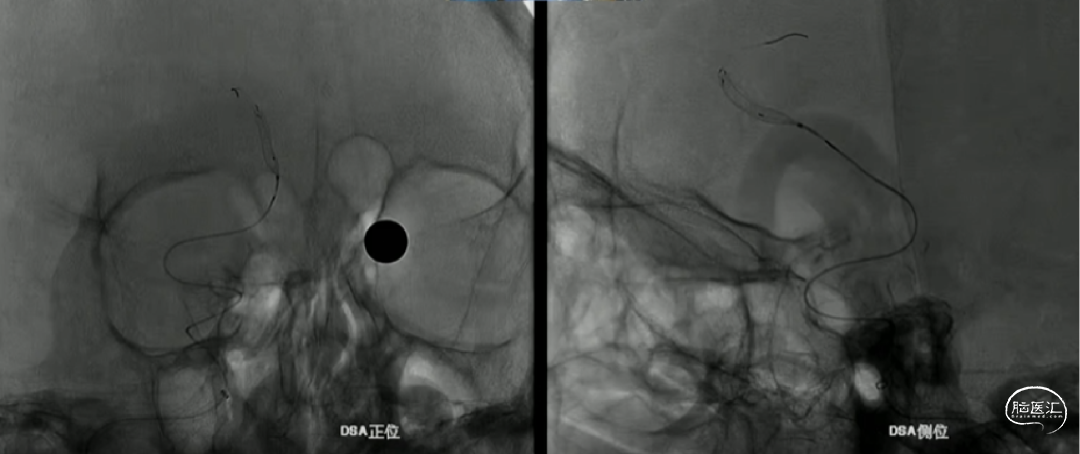

如意完全释放

支架整体释放后,贴壁良好,打开良好,无需再次按摩支架贴壁,故上高心玮DMC21微导管,回收带镍钛球囊的输送导丝。

术后即刻造影,动脉瘤滞留明显,载瘤动脉管腔通畅无狭窄,支架贴壁理想。

“如意”血流导向密网支架很好打开,镍钛小球助力支架更好的二次打开,支架释放中就能达到自膨打开,无需按摩,是一款各方面性能都不错的支架。

本例病例奇大脑前A3段动脉瘤,从大脑前动脉瘤起始段有广泛伴有动脉粥样硬化的斑块,血管路径过于迂曲,且颅内支撑导管的位置过低,仅位于C4段,无法提供很好的支撑性和力的传导功能,这样的情况会导致支架推送性能会有下降,释放中会降低可控性,对于这样的病例,颅内支撑导管上到更高,上至颈内动脉瘤末端或A1段会起到更好的帮助。